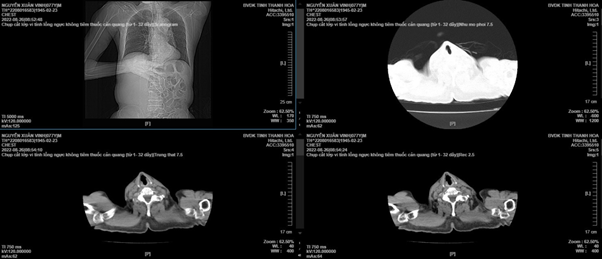

Hình ảnh khối phình trên phim chụp CT-scanner trước và sau can thiệp

Khối phình động mạch chủ bụng đoạn dưới các động mạch thận, đường kính khoảng 7-8 cm, bị vỡ 1 đoạn dài khoảng 4cm. Khối phình vỡ vào sau phúc mạc, tạo thành khối máu tụ khổng lồ chiếm hơn 1/2 bụng bên trái, bóc tách toàn bộ phía sau đại tràng xuống, hố thận trái, cơ thắt lưng chậu trái và lan rộng đến các động mạch chậu hai bên. Các bác sĩ cắt bỏ hoàn toàn khối phình động mạch chủ chậu, tái lập lưu thông động mạch chủ chậu với ghép mạch máu nhân tạo dạng chữ Y, nối giữa động mạch chủ – chậu trái và chủ – đùi bên phải.